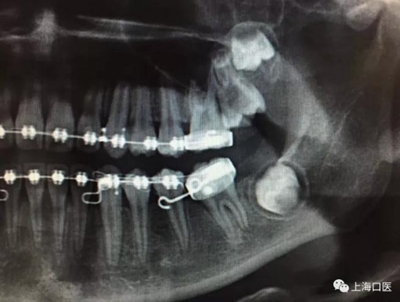

這是上海武廣增正畸工作室接診的一例非常規(guī)拔牙矯治病例,患者女性,初診年齡14歲。LL6殘冠拔除。LL7近中平移取代LL6,我們上傳了該患者一組下頜磨牙近中平移連續(xù)矯治過程的正畸X線片,與正畸界朋友分享。

來源:武廣增 上海口醫(yī)